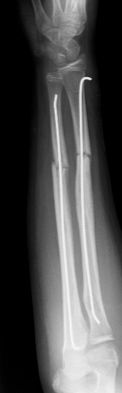

Las fracturas de ambos huesos del antebrazo al mismo nivel, con líneas de fractura oblicua-transversa o desplazamiento convergente son inestables y precisarán de tratamiento quirúrgico. En estos casos está indicado, dependiendo de la edad del paciente, el tratamiento mediante reducción y osteosíntesis. El enclavado intramedular elástico es el tratamiento de elección (Figura 15).

Figura 15: a-Imagen clínica de fractura de antebrazo derecho con gran deformidad. b- Radiografía donde se aprecia fractura de radio-cúbito de trazo transverso en el mismo nivel. c, d-Enclavado intramedular elástico. e,f- Imagen final con buena consolidación ósea.